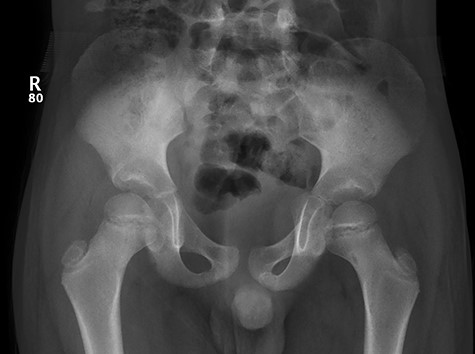

Patient was given adequate analgesia and routine blood tests were done (CRP 5.8 WBC 7.5x109). X-rays revealed small Lytic lesion with surrounding sclerosis at infero-medial aspect of left femoral neck in antero-posterior and lateral views (Fig. 1, 2).